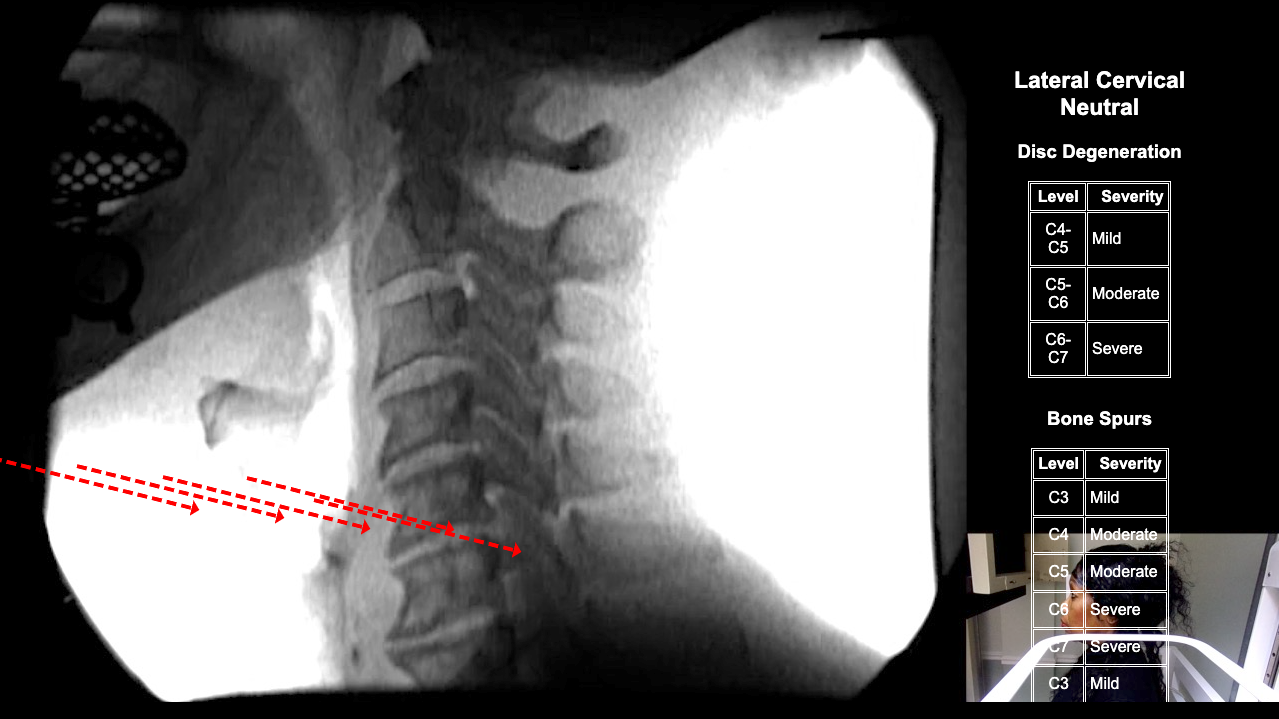

Home > Catherine Basseck 10-23-25